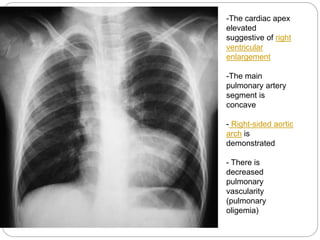

Chest Xray

 Findings on an x-ray diagnostic of tetralogy of

fallot include:

 Normal or decreased pulmonary vascularity

 Concave pulmonary artery segment

 A right sided aortic arch may also be present.

 There is pruning or reduction in the prominence of

the pulmonary vasculature over time

Chest X-Ray

 Plain films may classically show a "boot shaped"

heart with an upturned cardiac apex due to right

ventricular hypertrophy and concave

pulmonary arterial segment

-The cardiac apex

elevated

suggestive of right

ventricular

enlargement

-The main

pulmonary artery

segment is

concave

- Right-sided aortic

arch is

demonstrated

- There is

decreased

pulmonary

vascularity

(pulmonary

oligemia)